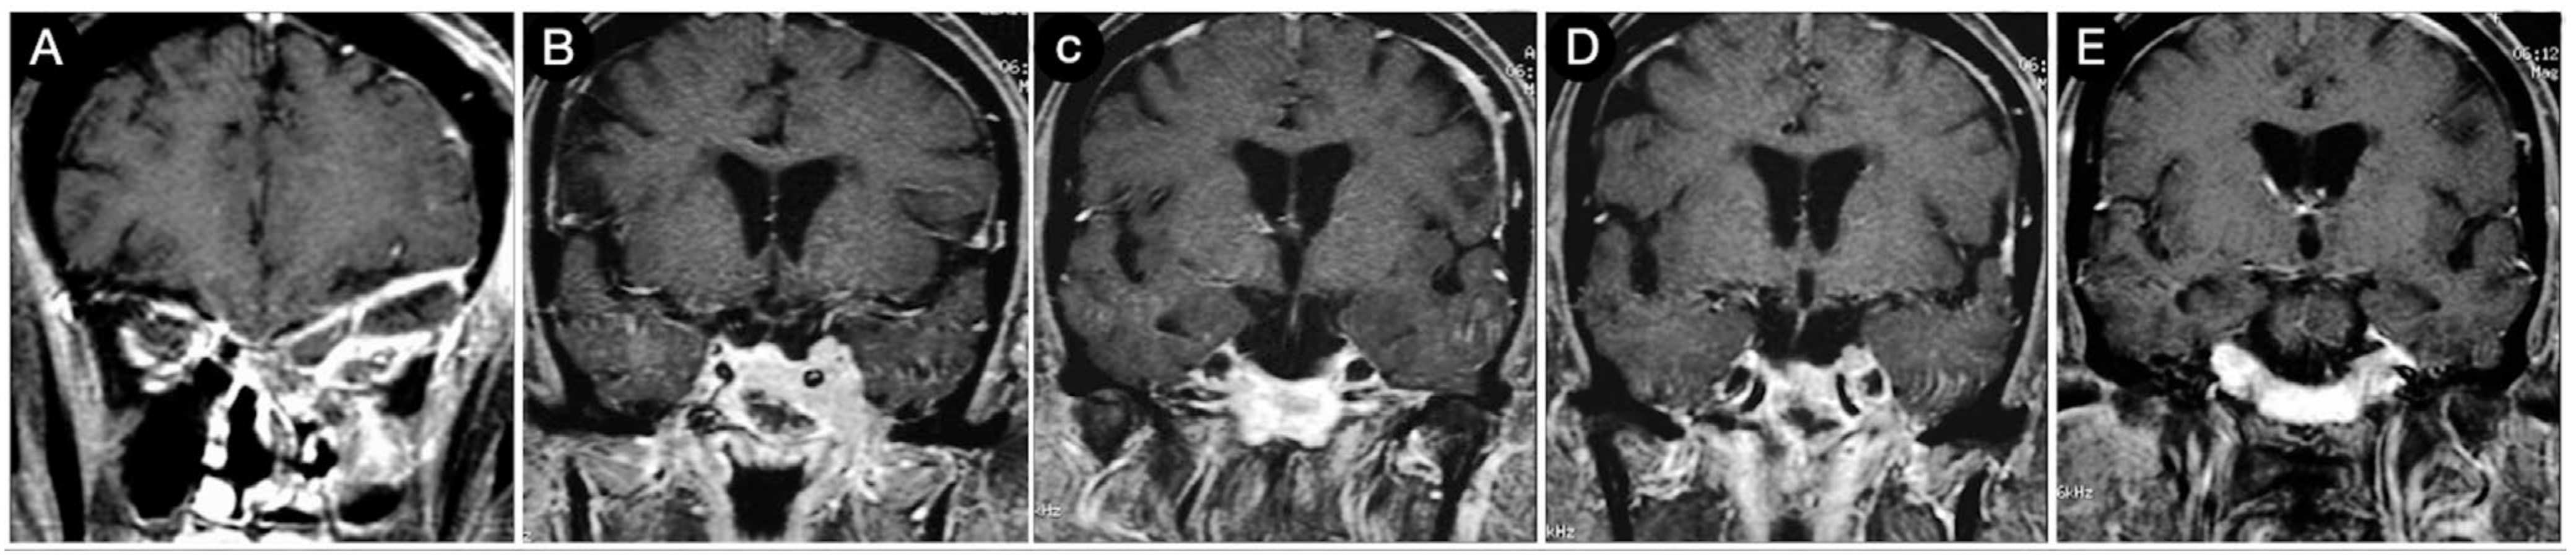

Case #8: Aggressive ACTH Tumor with Multiple Recurrences